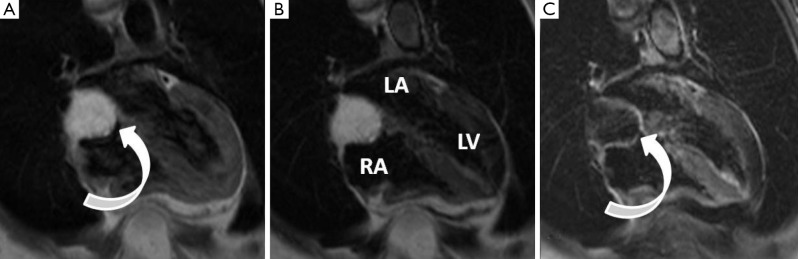

Typical MRI features are a well-defined spherical or ovoid mobile lobulated mass within either atria, sometimes prolapsing through the atrioventricular valve orifice in diastole. They usually appear hypointense to the blood pool on SSFP sequences (2). T1 and T2-weighted images usually show a heterogeneous appearance because of the combination of tumour tissue, necrotic elements and foci of haemorrhage and calcification (40-42) (Figure 1). First pass perfusion is usually absent and LGE is often multi-focal and patchy although may sometimes be homogeneous.

Figure 1.

Large left atrial/left atrial appendage myxoma. (A) Axial T1-weighted black blood image showing a well-defined slightly heterogeneous signal lesion within the body of the left atrium (arrows); (B) coronal T1-weighted black blood image showing the myxoma filling the left atrial appendage and filling a large portion of the left atrium (arrows); (C) coronal T1-weighted delayed phase image acquired 15 minutes post gadolinium showing patchy central foci of enhancement (arrows). Ao, aorta; LA, left atrium.